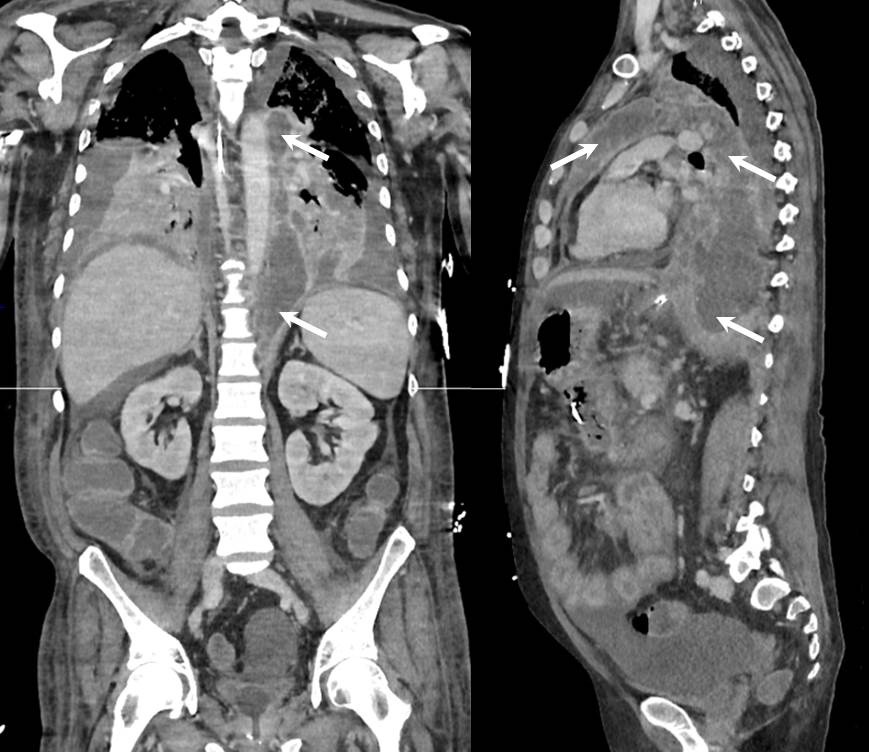

Three weeks after the hospital admission, the patient experienced fever, confusion and respiratory distress requiring mechanical ventilation and intensive care. A new CT-scan revealed bilateral pleural effusion, a non compressive pericardial effusion and a large posterior and anterior mediastinal collection along the left side of aorta spreading from the aortic hiatus to supraaortic vessels (Figure 1, arrows). Blood cultures were positive and grew to Klebsiella spp. A mini-thoracotomy was performed and confirmed the diagnosis of infected mediastinal pancreatic pseudocyst with high level of lipase (49 340 UI/L) and local microbiological samples positive for the same bacteria. Subsequently, the whole mediastinum was washed and drained using a large left thoracotomy.